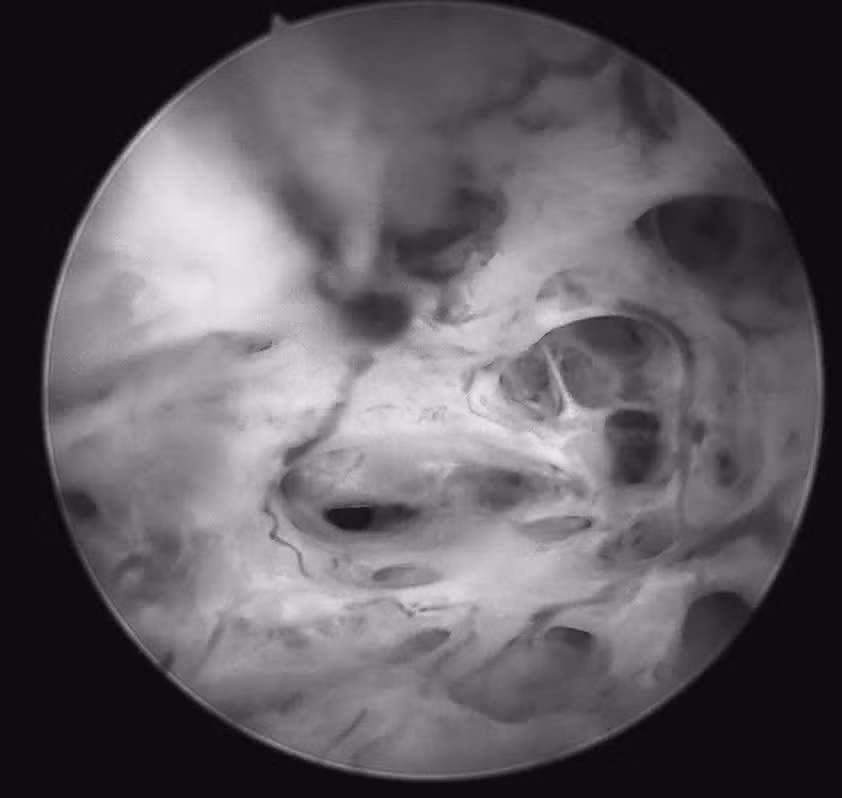

ngang-vang-3.jpg

Hình ảnh tổn thương qua nội soi - Ảnh BVCC

Quá trình soi diễn ra an toàn, nhẹ nhàng. Bệnh nhân hoàn toàn tỉnh táo và có thể quan sát trực tiếp hình ảnh buồng tử cung trên màn hình: niêm mạc nham nhở, tăng sinh không đồng đều, nhiều mạch máu bất thường, những dấu hiệu gợi ý tổn thương ác tính. Mẫu sinh thiết được lấy ngay trong quá trình soi để làm xét nghiệm mô bệnh học.

Năm ngày sau, kết quả trả về là điều không ai mong muốn: Ung thư niêm mạc tử cung.